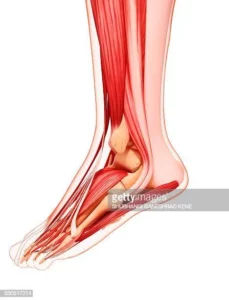

The Achilles tendon connects the Achilles muscle to the heel. Excessive stress or a tight or fatigued calf muscle can result in microtrauma, degeneration, and even inflammation of the tendon- a condition called Achilles Tendonitis/Tendinosis. This condition can be caused by prolonged walking, excessive running, jumping, and walking hills.

Research suggests that Achilles tendinosis, a similar condition, may cause a gradual onset and long recovery. Tendinosis, a chronic degenerative condition, is not like tendonitis. It is characterized by no inflammation and is a chronic condition. Tendinosis is more common than tendinitis, as tendon pain is often not accompanied with the typical inflammatory signs such swelling, redness and warmth.

The Achilles tendon may be torn (or ruptured) by a forceful contraction of the calves muscle. This is common in athletes who play basketball or baseball. The patient frequently describes feeling like they were hit or kicked in their lower calf. The tendon above the heel is tender and there is pain.